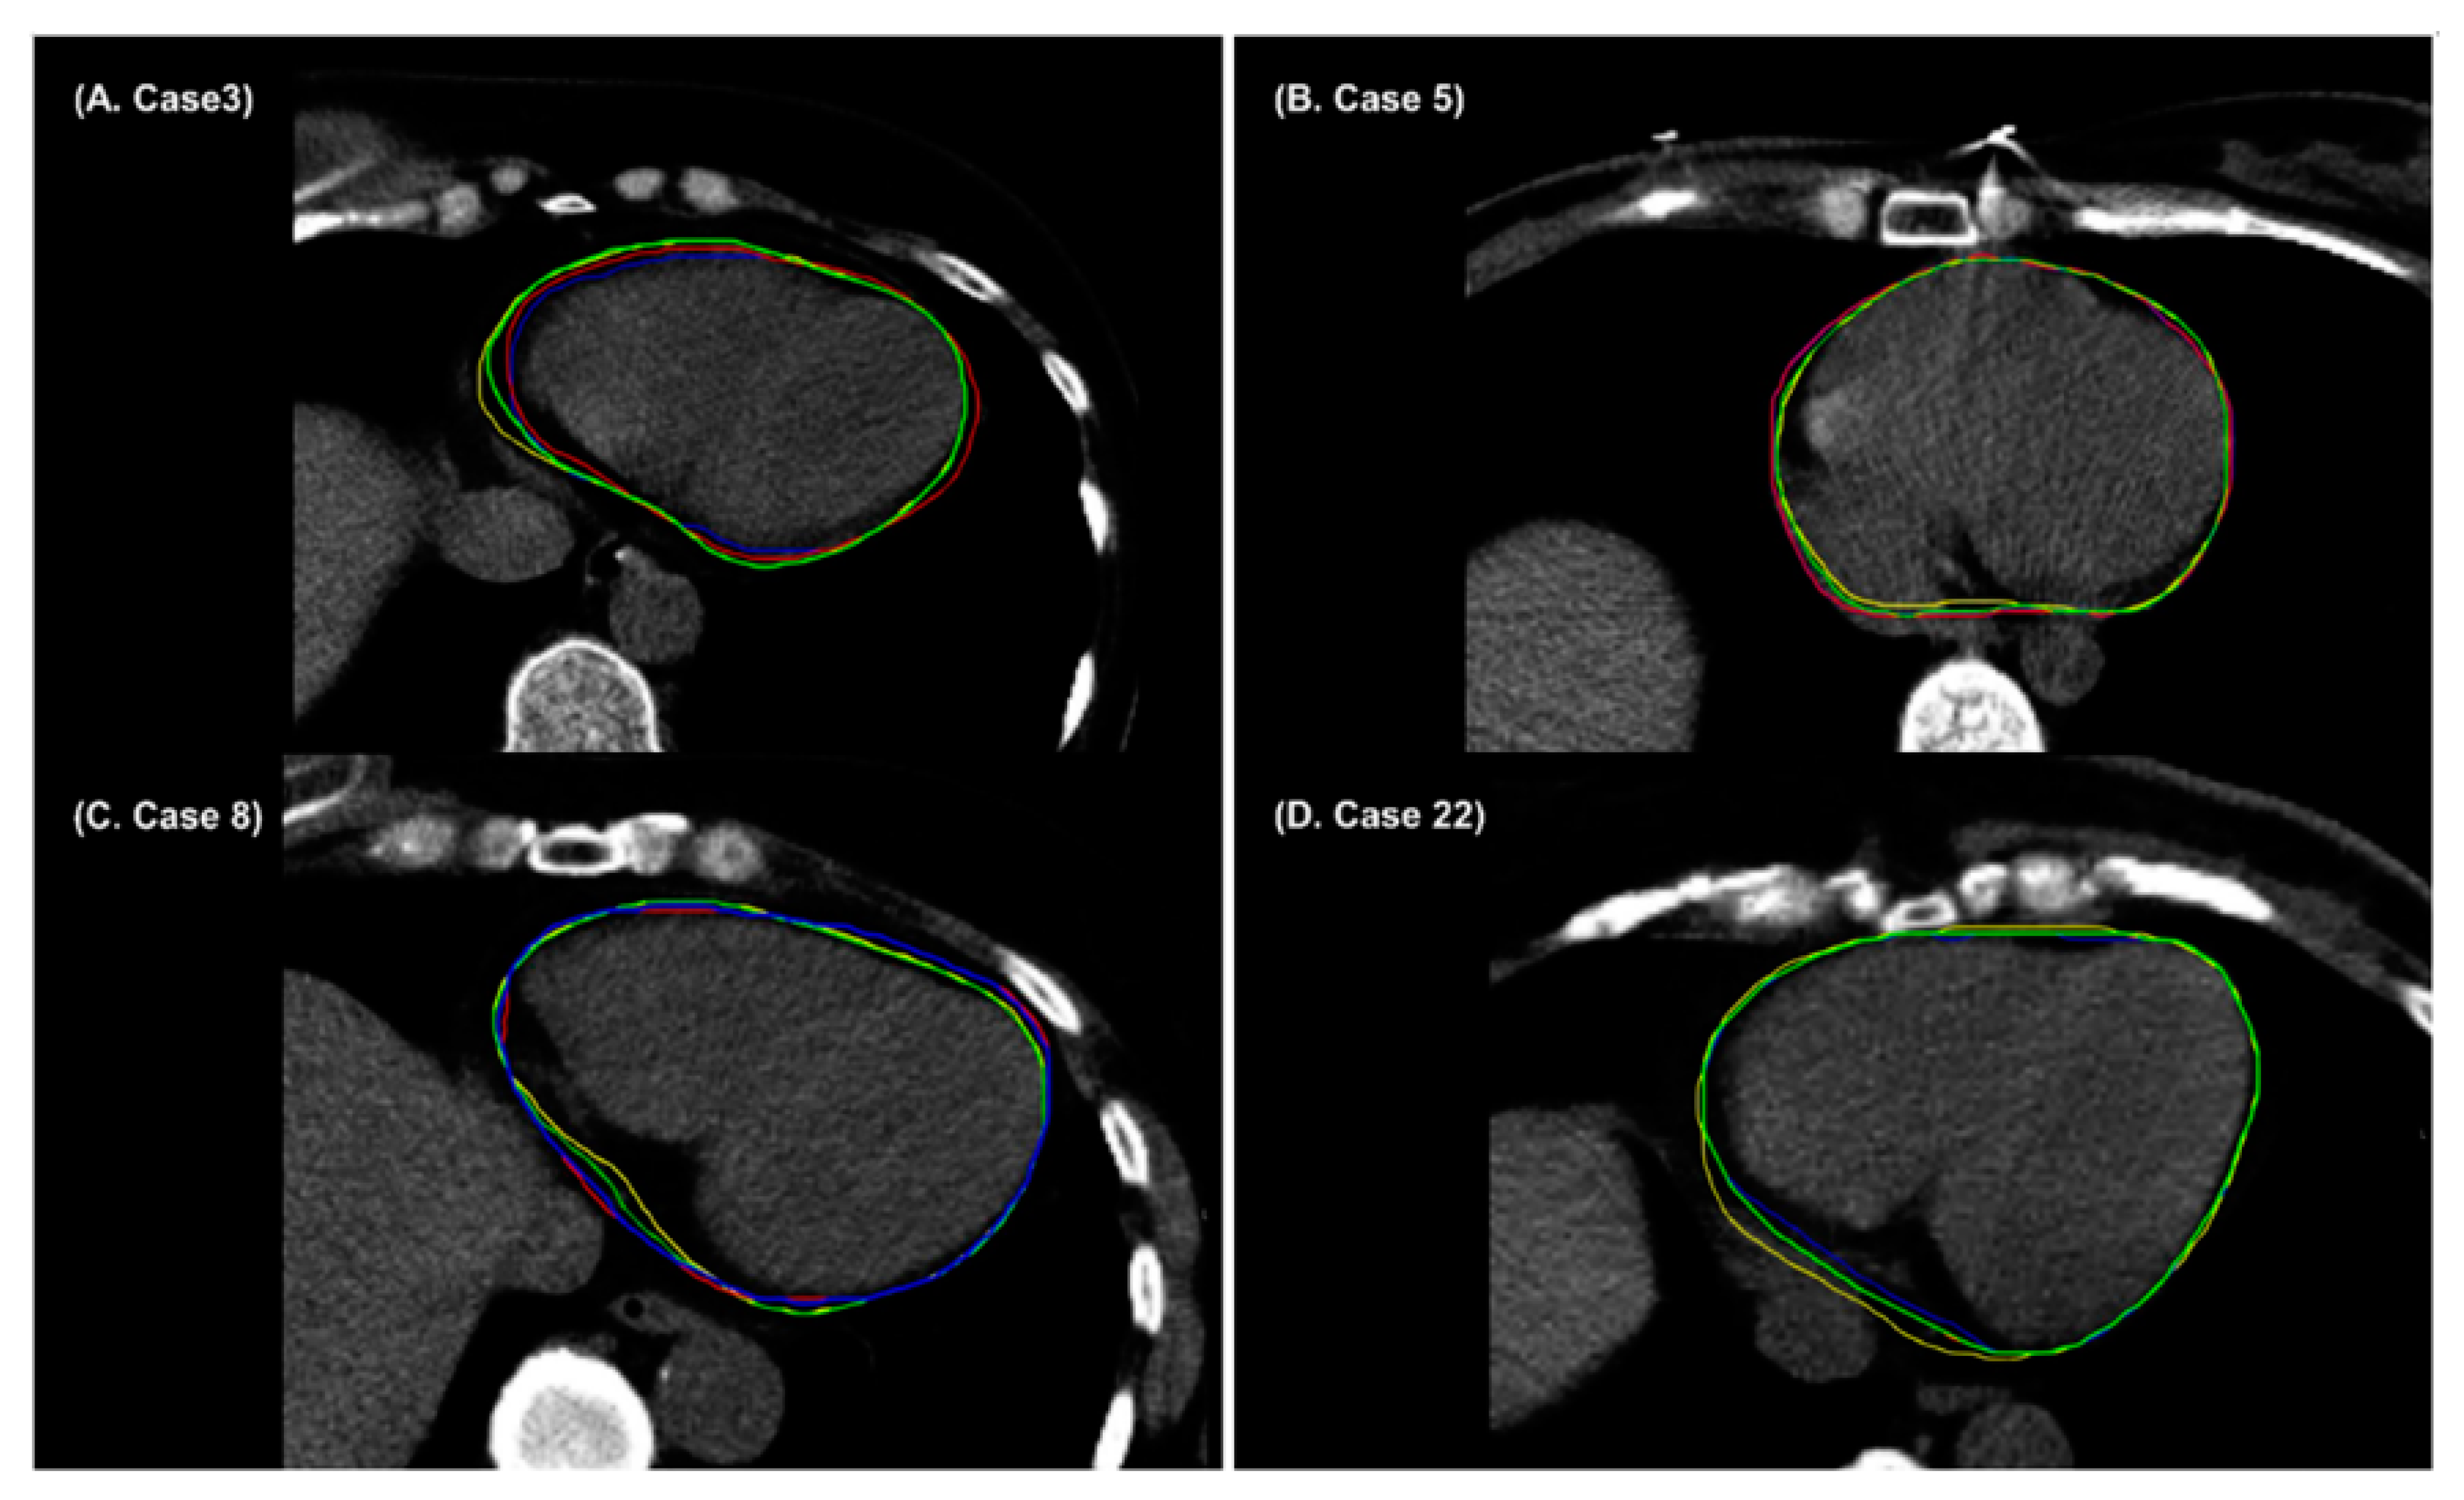

- Chung, S.Y.; Chang, J.S.; Choi, M.S.; Chang, Y.; Choi, B.S.; Chun, J.; Keum, K.C.; Kim, J.S.; Kim, Y.B. Clinical feasibility of deep learning-based auto-segmentation of target volumes and organs-at-risk in breast cancer patients after breast-conserving surgery. Radiat. Oncol. 2021, 16, 1–10. [Google Scholar] [CrossRef] [PubMed]

- Choi, M.S.; Choi, B.S.; Chung, S.Y.; Kim, N.; Chun, J.; Kim, Y.B.; Chang, J.S.; Kim, J.S. Clinical evaluation of atlas-and deep learning-based automatic segmentation of multiple organs and clinical target volumes for breast cancer. Radiother. Oncol. 2020, 153, 139–145. [Google Scholar] [CrossRef]